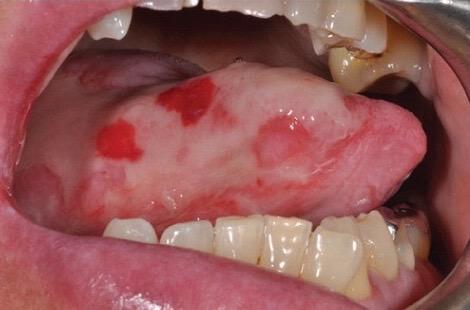

Mucositis

• Inflammation of the mucosal lining; affects the mouth, pharynx, and GI tract

• Most debilitating side effect of chemotherapy; needs pain management, progressing to painful ulcerations ultimately altering nutrition

• Prevention: Routine oral hygiene, saline rinses, use of soft toothbrushes or toothettes

• Treatment: Emollients/balms for the lips, analgesic oral rinses, cool compress